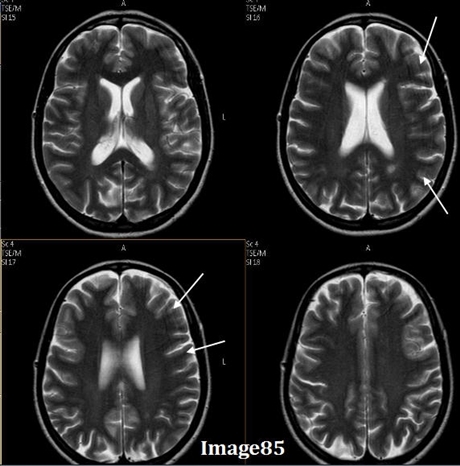

he arrows in Image 85 point to what kind of artifact?

Gibbs truncation